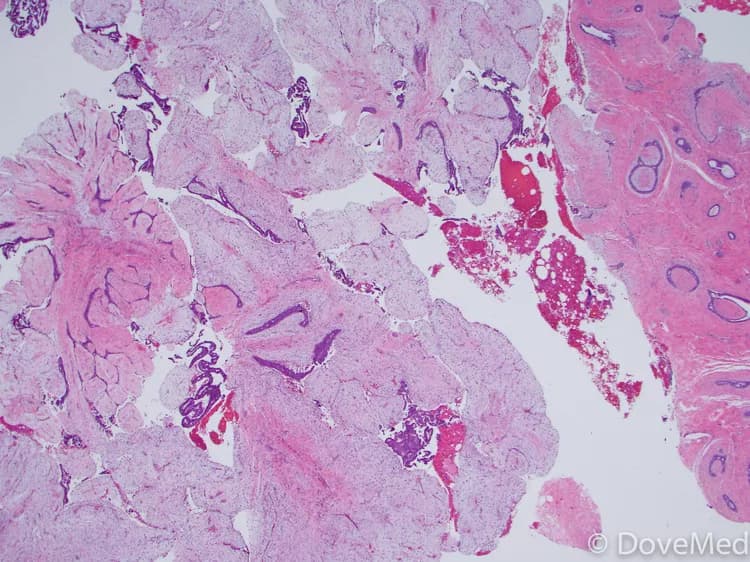

• Intraductal papillomas: They are small growths that occur in the breast ducts

• Intraductal papillomas are much smaller lumps made of glandular tissue, fibrous tissue, and blood vessels. These lumps grow in the breast ducts and cause discharge from the nipple